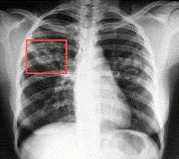

Приложение

2.

Заражённые легкие.

Здоровые легкие.

3

Заражённые лёгкие.